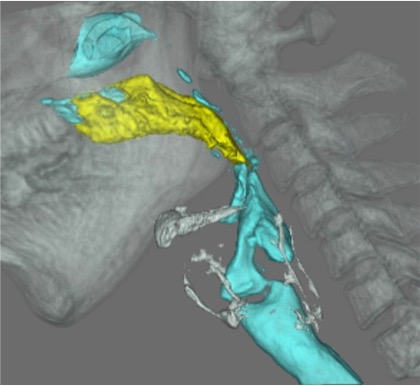

4. 嚥下CT

320列CTを用いて嚥下動態の4次元的観察を行います。飲み込み時の嚥下関連器官の動態を経時的に詳細に評価することができます。当検査は、藤田医科大学病院にて行っています。